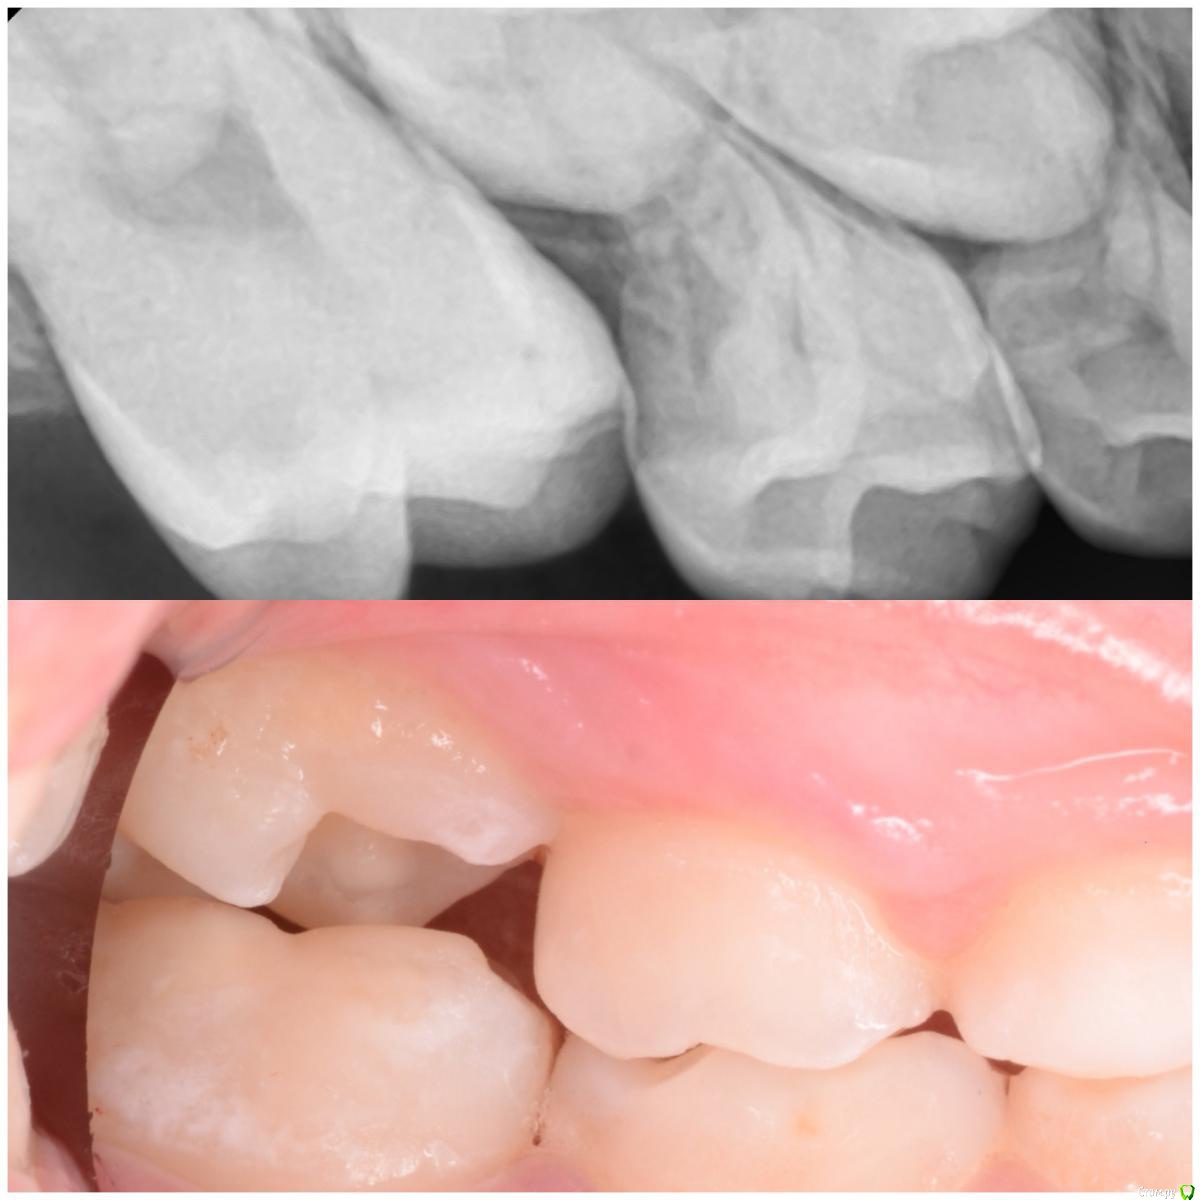

CRAZYDUCK Опубликовано 5 июня, 2018 Автор Поделиться Опубликовано 5 июня, 2018 Про эктопию верхних 6 зубов ( импактные шестые зубы). Встречается не так уж и редко . Для общего развития всем будет полезно . Эктопия ( импактные верхние 6 зубы).просто говоря - верхние 6 зубы из-за дефицита места на верхней челюсти или из-за оси прорезывания направленной медиально , способствуют резорбции корня 6.5 или 5.5. Эктопия может быть обратимой и необратимой . Но после 8 лет ( но возраст зубной может отличаться от антропометрического, поэтому смотрим на сроки прорезывания других постоянных зубов у конкретного ребёнка ) ортодонтическая коррекция нужна ( процесс необратимый). Методы устранения -Без удаления временного 5 возможно применение частичной брекет-системы , которая нормализует ось прорезывания 6 зуба ( в литературе можете найти всякие латунные сепараторы , но это история и мне кажется сложнее брекет-системы ). На первых двух фото показан случай эктопии 1.6 , который не требует удаления 5.5 . А вот дальше показан случай эктопии 2.6 , требующий удаления 6.5. Каждый случай индивидуален . ‼️коллеги , важно помнить , что 2.6 в случае удаления 6.5 полностью заблокирует зачаток 2.5 ‼️здесь обязательно нужна будет помощь ортодонта ( немедленная или отсроченная ортодонт с родителями решат ). Ну а 5 временные зубы после такой подлости со стороны шестёрок могут быть причиной воспаления ( хотя сами пятые могут быть инактными ). 2 Ссылка на комментарий

CRAZYDUCK Опубликовано 5 июня, 2018 Автор Поделиться Опубликовано 5 июня, 2018 (изменено) Про эктопию верхних 6 зубов . Изменено 5 июня, 2018 пользователем CRAZYDUCK Ссылка на комментарий